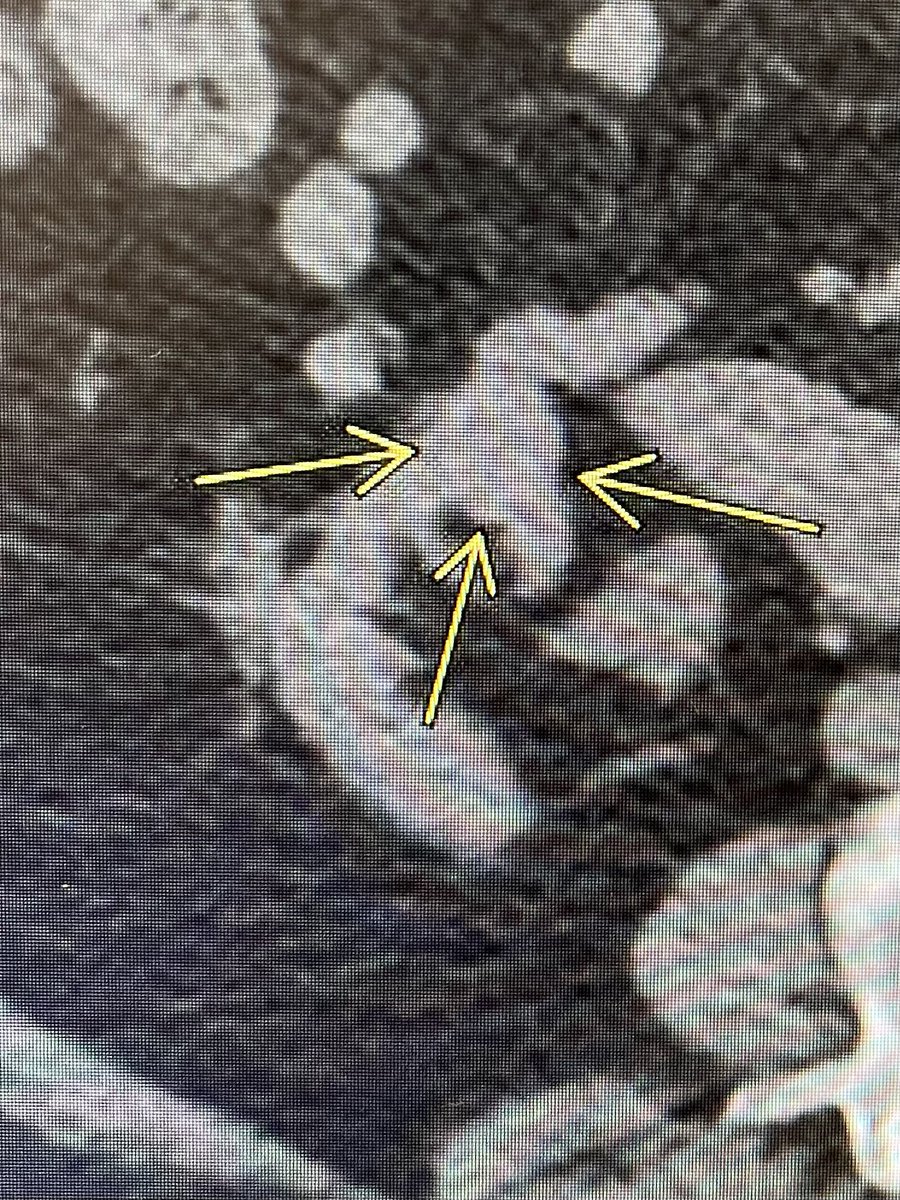

One of the 1st studies in healthcare using @HoloLens 2, supported by @RSNA. #AugmentedReality guidance improves procedure times and radiation dose. Med students also instantly elevated to #IRAD attending level! @dotter_IR @Penn_IR @PigiLab @SIRRFS rdcu.be/b9p98